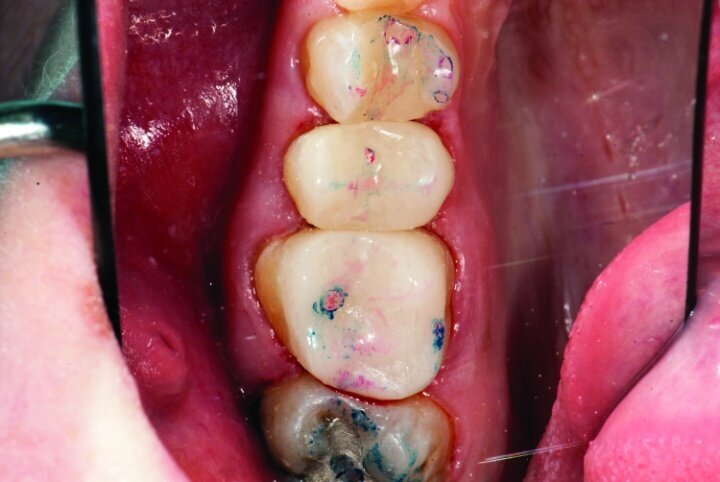

Gross occlusal reduction was completed using a KS7 bur to the depth cuts (Figs. 4–8b, 9c). Adequate clearance was verified with a 2 mm prep check from Common Sense Dental Products.

After gross occlusal reduction was completed, the remaining enamel ring was measured (Figs. 9a, b). The enamel rings were noted to be 1.5 mm, and the teeth were prepared for adhesively retained restorations. If the enamel rings were less than 1 mm, the teeth would have been prepared on the axial walls to create retention for cohesively retained crowns.